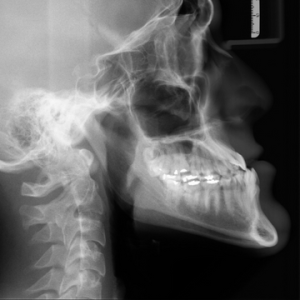

Con un número cada vez mayor de dientes anteriores traumatizados tratados con procedimientos de endodoncia regenerativa hoy en día, se espera que el movimiento ortodóncico de dichos dientes se...